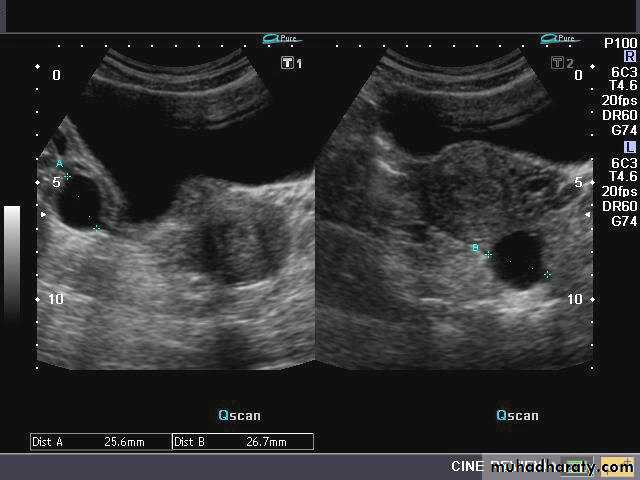

Ovarian hyperstimulation syndrome (OHSS):

This young adult female patient was examined to evaluate the uterus and ovaries. She was under treatment for infertility and was using gonadotropins. Ultrasound images of the ovaries show grossly enlarged ovaries with large cysts (measuring 2.6 to 3 cms.) in both ovaries. These ultrasound findings are diagnostic of OHSS or ovarian hyperstimulation syndrome.

• Ovarian hyperstimulation syndrome (OHSS):

The ultrasound image again show hyperstimulated ovaries. Both ovaries are grossly enlarged and cystic.